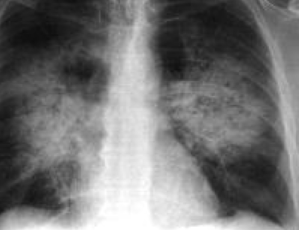

At high altitude, this adaptive mechanism seems to go wrong. Virtually all the alveoli sense decreased availability of oxygen after an acute exposure to high altitude because air drawn into the lungs at that altitude has a lower partial pressure of oxygen. This triggers global pulmonary arterial vasoconstriction that increases the blood pressure in the pulmonary arteries. Increased pressure, along with inflammatory changes that accompany hypoxia, causes a characteristic pattern of high altitude related pulmonary edema, most notably centered around the right pulmonary artery.

Hypoxic vasoconstriction evolved at low altitude, as a way to compensate for regional pulmonary hypoxia, e.g. during bacterial infection. We might imagine this compensatory mechanism might also occur among those with lung infection at high altitude. In other words, if hypoxic pulmonary vasoconstriction is an adaptation to infection or other lung injury that is pathological at high altitude, it would follow that infection would predispose to HAPE. A recent paper described this exactly. Ebert-Santos described a phenomenon termed as MRHAPE , or mountain resident high altitude pulmonary edema. In MR HAPE, acclimatized mountain residents show signs of HAPE on chest radiographs when they get sick with a respiratory virus. These high altitude residents otherwise show no pulmonary symptoms while living at high altitude. This is exactly what we see in this article. Since I live at 6000 feet elevation in Albuquerque New Mexico, and care for individuals living at even higher elevations, I suspect that I have had many patients who fall into this category that have not been recognized as MR HAPE.

Probably, at least for the most severe cases. Recall that hypoxic pulmonary vasoconstriction evolved to protect us when part of the lung is diseased and other parts of the lung remain healthy, e.g in garden variety bacterial pneumonia. In the severe pulmonary syndrome driven by COVID-19, when no part of the lung is spared, that compensation can become pathologic, as it does at extreme altitude. Increased pulmonary arterial pressures, in combination with inflammation driven by HIF-1, cause capillary leak and edema, resulting in a vicious cycle of worsening hypoxia and respiratory failure.